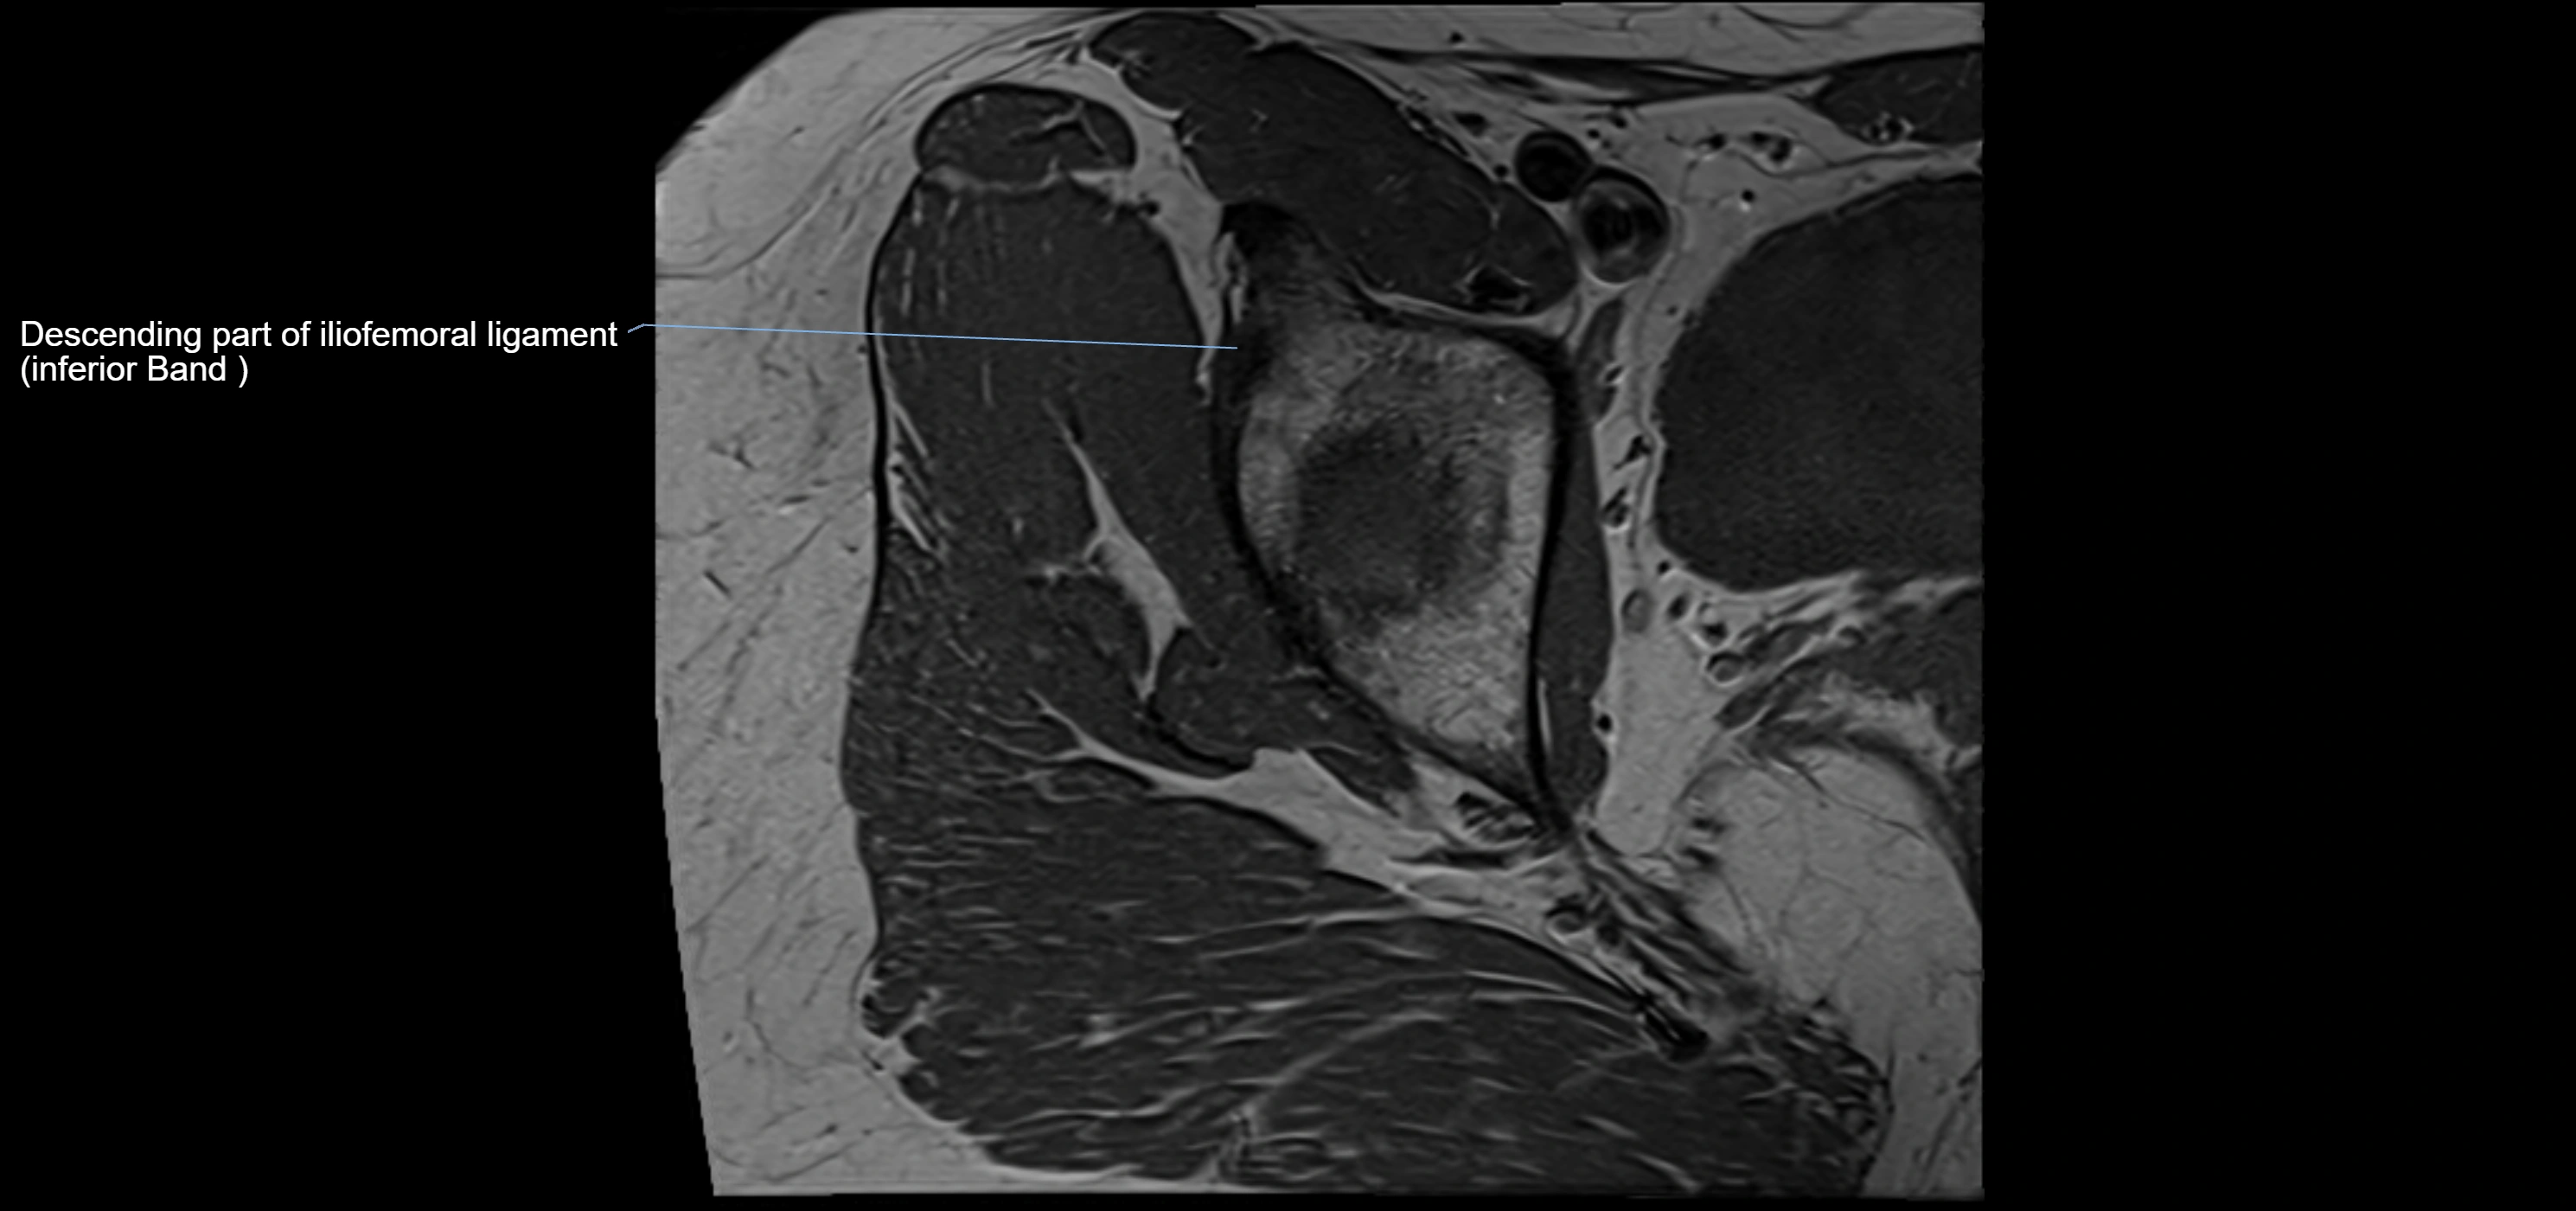

Acetabular labrum

The acetabular labrum is a fibrocartilaginous ring that surrounds the rim of the acetabulum in the hip joint. It deepens the hip socket, increases joint stability, and maintains a suction seal that preserves negative intra-articular pressure. Structurally, the labrum transitions from hyaline cartilage of the acetabulum to dense fibrocartilage at its free edge.

MRI Appearance

T1-weighted images:

• Labrum: low signal intensity (dark)

• Surrounded by intermediate signal joint fluid (bright on arthrogram)

• Tears: linear or focal areas of intermediate-to-high signal interrupting labral continuity

T2-weighted images:

• Joint fluid: bright, making labral tears visible as fluid extending into or around labrum